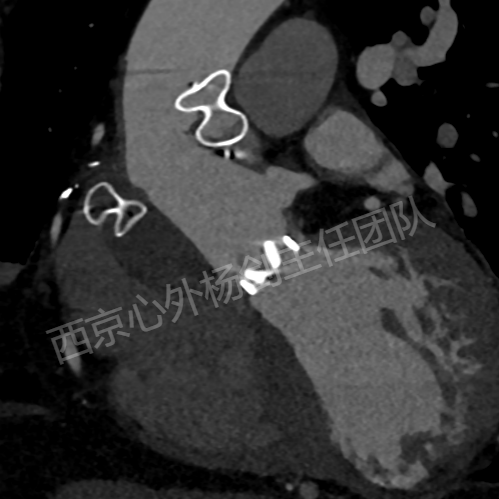

患者李某某,男,61岁,现病史:高血压15年,15年前行主动脉瓣置换术,13年前行升主动脉置换术、冠状动脉旁路移植术。主因心脏瓣膜术后15年,突发胸闷气短20天入院。检查提示:主动脉夹层动脉瘤,主动脉瓣位机械瓣位置、动度未见异常,升主动脉位人工血管上段吻合口漏,原有升主动脉管壁与人工血管之间液区,向右房分流,肺动脉高压(收缩压约51mmHg)。EDV: 192ml, ESV:102ml, FS:23%, SV:89ml。

术前CT评估

术后CT评估